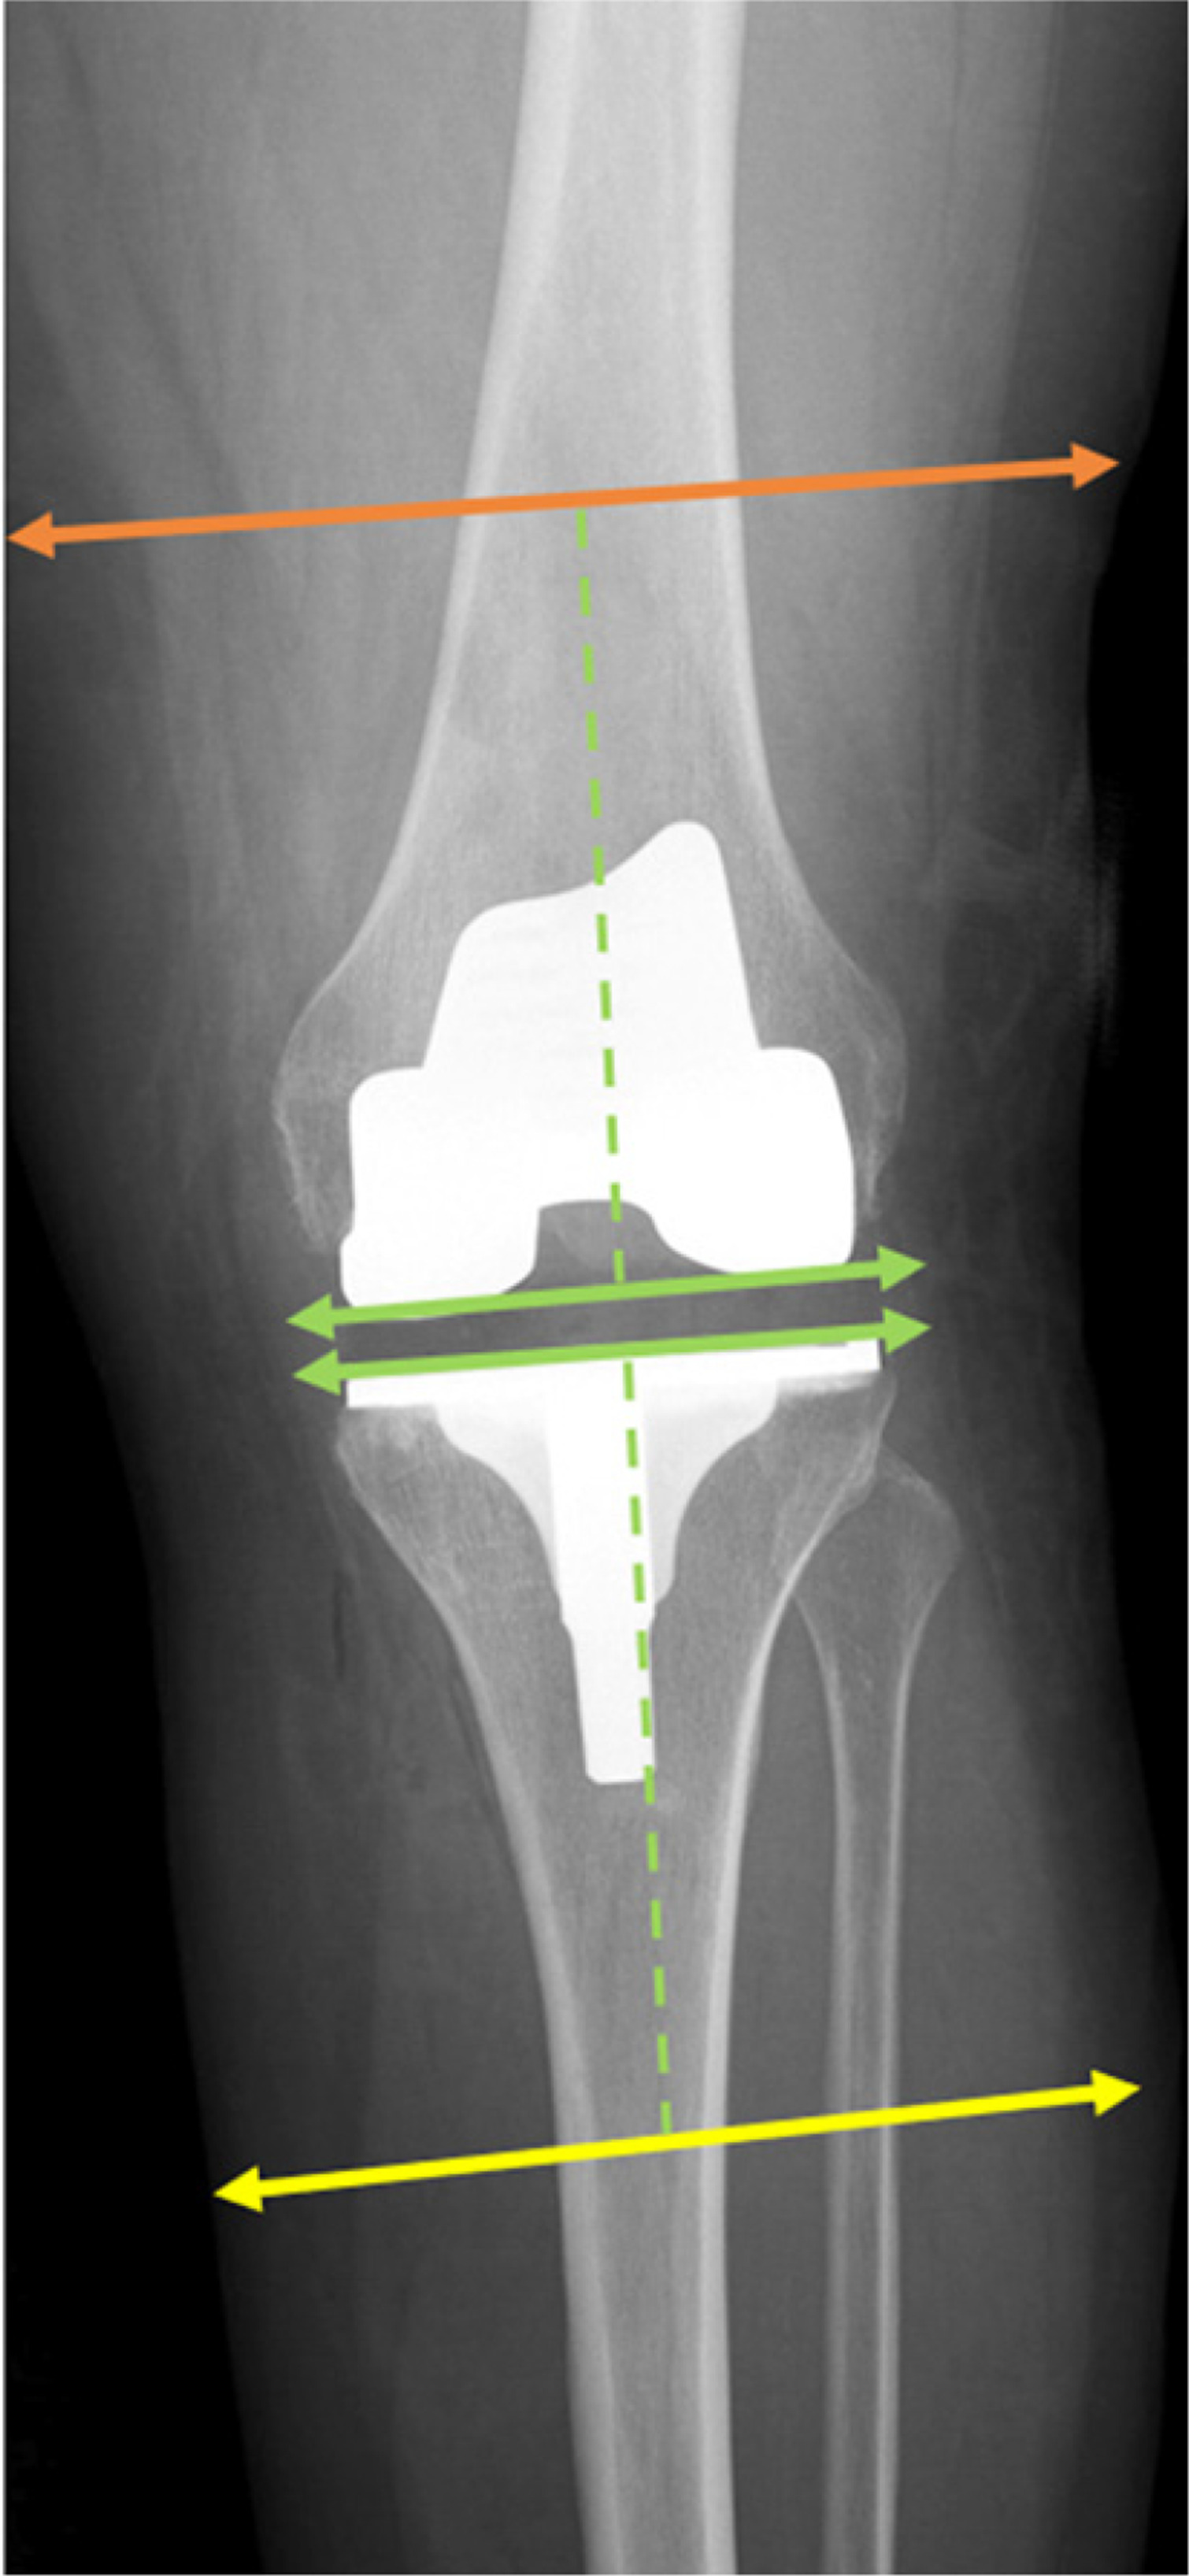

Fig. 1

Antero-posterior view of the lower limb measurement areas. The green dashed line marks a distance of 10 cm from the intercondylar line and the tibial plateau, marking the femoral and lower leg measurement regions indicated by the orange and yellow lines, respectively.